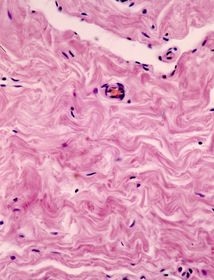

Tejido conjuntivo denso no ordenado de la glándula mamaria. Se observa el aspecto característico ondulante de los haces de fibras colágenas